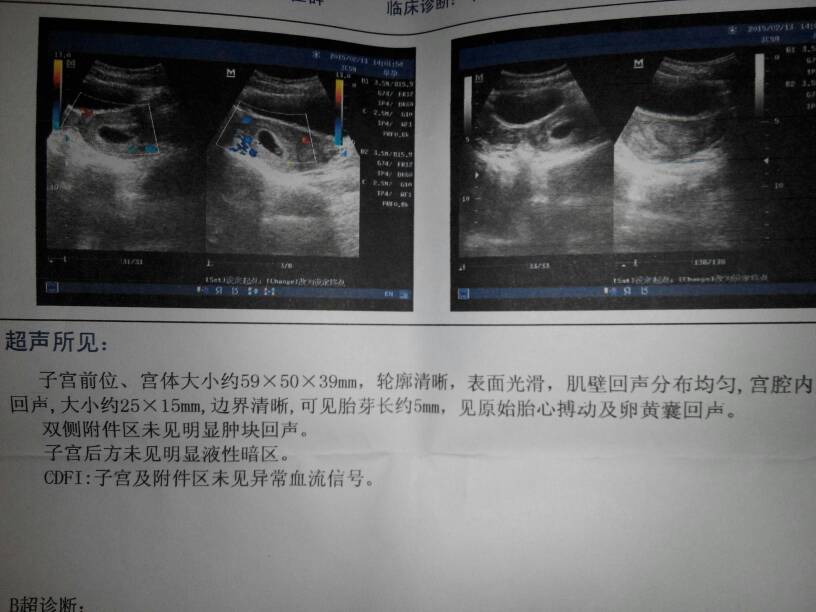

宝妈们,医生们,来看看我怀孕多久了!末次月经是12-21号,医生说到15我就60天了,按理说我应该没有那么快吧??